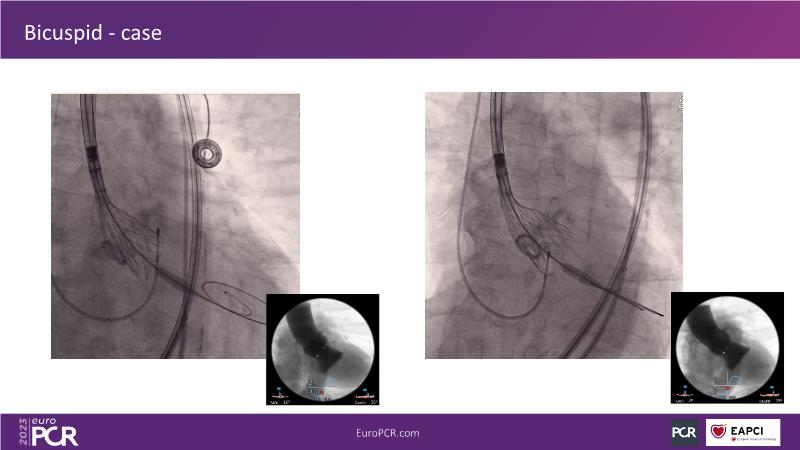

Discover the key factors to consider in selecting the optimal valve and implant technique for transcatheter aortic valve implantation (TAVI) to achieve optimal procedural outcomes. Gain insights into the impact of device choice and implantation technique on coronary access following TAVI and learn valuable strategies for tailoring your TAVI technique to complex scenarios, including bicuspid aortic valves, large and calcified anatomies, and ensuring coronary access.

- To learn how to tailor your TAVI technique to complex situations: bicuspid aortic valves, large, calcified anatomies and coronary access